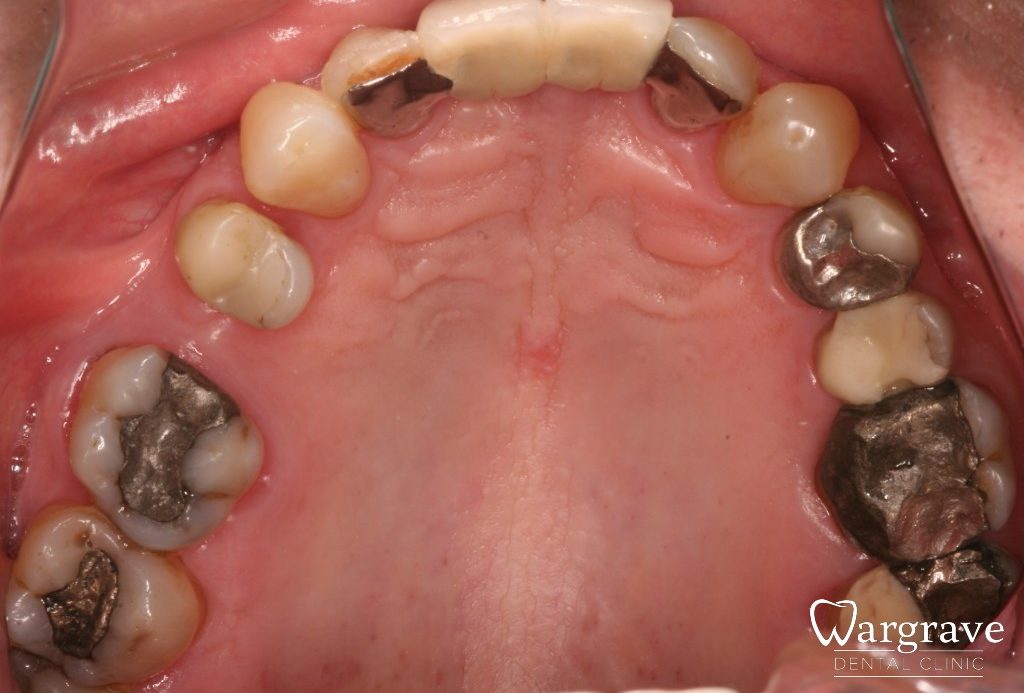

Posterior rehabilitation

This patient wished to protect all his large posterior fillings. 10 new crowns were provided on the premolars and molars, leaving all his front teeth as they were.

before

after